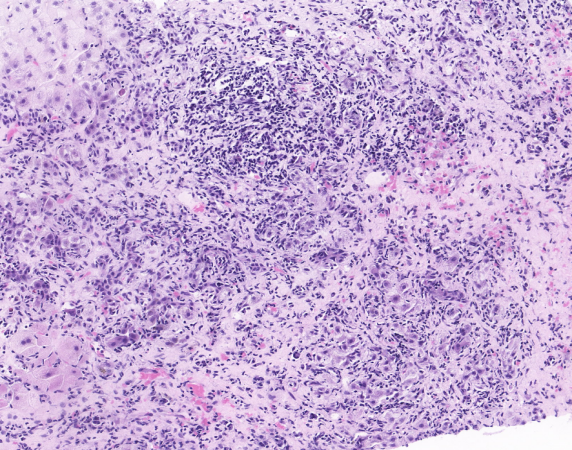

2025-05至我院就诊,行肝穿刺活检病理示肝小叶结构中-重度紊乱,小叶内肝细胞中度浊肿及多个碎片状坏死,局部碎片状坏死融合成不规则大片状,可见中-重度界板炎及所谓的“玫瑰花结”样肝细胞变性团(见图1)。计算自身免疫性肝炎简化评分7分,诊断为自身免疫性肝炎,予

图1 肝脏穿刺病理图片